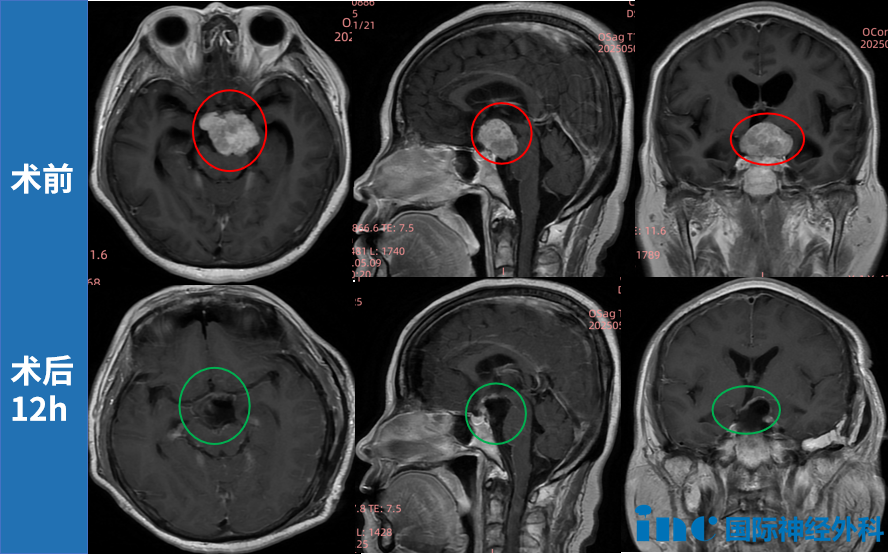

赵女士因眼前黑影症状检查发现鞍区肿瘤病变。鞍区作为蝶骨鞍状结构区域,汇集垂体、视神经与视交叉、下丘脑等重要解剖组织,属于颅底解剖中复杂性较高区域。肿瘤向前上方推挤视交叉结构,向前下方压迫垂体柄,向后方压迫脑干组织,并与动眼神经、滑车神经、三叉神经紧密相邻,同时毗邻颈内动脉及基底动脉系统。

INC福教授采用显微镜与神经内镜双镜联合技术,在完整保留听力功能与面神经功能前提下,成功实现肿瘤精准切除,术后病理检查确诊为脑膜瘤。